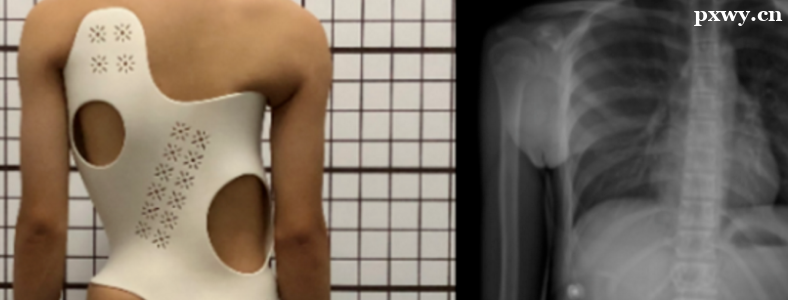

脊柱侧弯几岁能看出来?脊柱侧弯是一种常见的骨骼问题,通常在青少年时期出现。在这个阶段,身体的骨骼和肌肉系统仍在发育,因此容易出现脊柱侧弯。但是,脊柱侧弯并不总是明显的,有时需要在特定的体态或X光检查中才能发现。

一、脊柱侧弯的发现时间

脊柱侧弯通常在青少年时期出现,但也可能在成年后逐渐发展。这种骨骼问题可能导致身体扭曲、肩膀高度不一、腰背部疼痛等症状。一般来说,大多数人的脊柱都会有一定的侧弯,但当侧弯角度大于10度时,就可能对身体健康造成影响,需要接受治疗。

当脊柱侧弯角度大于10度时,需要接受专业的治疗。治疗方法包括保守治疗和手术治疗。保守治疗包括物理治疗、药物治疗和支具治疗等。手术治疗则是通过手术纠正脊柱的形态,从而达到治疗的目的。在接受治疗时,应该选择正规的专业医院进行治疗。